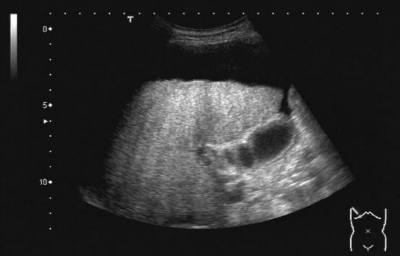

腹部超音波像を別に示す。この患者の血液検査項目で低値と予想されるのはどれか。

a. アンモニア

b. γ-グロブリン

c. 血小板

d. 総ビリルビン

e. PT-INR